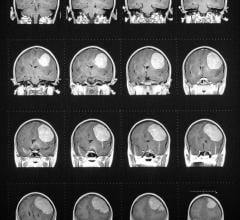

Contrast media, also called contrast agents, are used to enhance the blood and perfusion in tissues. This includes iodine based contrast for on computed tomography (CT), gadolinium based agents for MRI and lipid bubble contrast agents used in ultrasound.